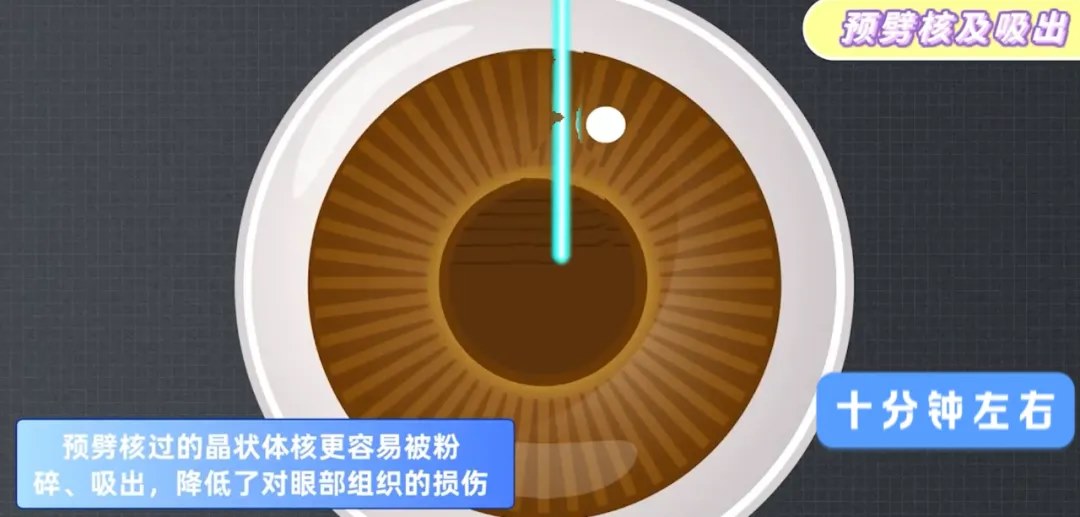

针对硬核,膨胀期,过熟期白内障、先天性白内障、年轻人白内障以及糖尿病白内障患者,相比传统手术,飞秒激光白内障手术更有优势。

传统的白内障手术,在超声乳化的关键步骤制造切口和撕囊时,都是依靠医生手动操作。所以,医生的经验和技巧非常重要,切口会影响恢复速度和术后视力,容易产生机械变形和渗透,而手工撕囊的质量影响术后并发症和视觉质量。

随着技术发展,以飞秒激光辅助白内障手术技术为代表的,前沿手术方式正受到越来越多人的青睐。

飞秒激光可以代替医生的手工切口,预先分割囊膜内的混浊晶体,整个过程都有电脑扫描成像技术辅助,可以准确地制造切口并撕囊,使其光滑平整,还可以利用飞秒激光去除患者部分散光问题,再用超声波去除晶体。